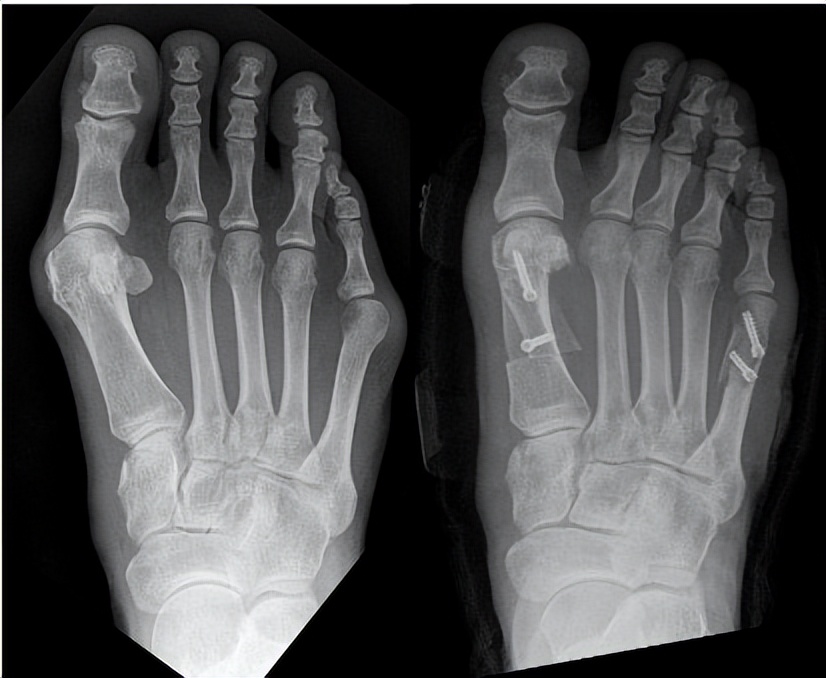

然后如果有哪种情况,他是可以通过手术来得以矫正的呢,就是图中这样子的情况,脚是有大脚骨,就是拇外翻,然后小踇趾外侧也会有凸起,我们看到这张x光片,可以通过这个情况我们能看到这脚是呈个骨头呈扇形分布。

正常状态下其实我们有一点点的角度,就是第1跖骨 第2跖骨之间有一点点角度,但是这个角度在7度以内,但是类似于这样这种角度就特别大,然后第四五跖骨现在夹角也较大。

那我们可以通过手术缩小第一二跖骨间的夹角,通过手术缩小第四五跖骨间的夹角,那把这两个夹角缩小以后,脚确实会窄许多,但有一些也要根据情况来。

大脚骨小脚骨术后

昨天有朋友就说,我想要把脚缩窄1厘米,是否可以做到,有一些可能确实可以做到,就是他第一二跖骨夹角比较大,第四五跖骨间的夹角也比较大。

一边缩个7毫米一边缩个3毫米,这是可能可以达成,但如果说两者之间的夹角都很小,基本接近正常,那这种情况你想要去把它缩小,难度就比较大。